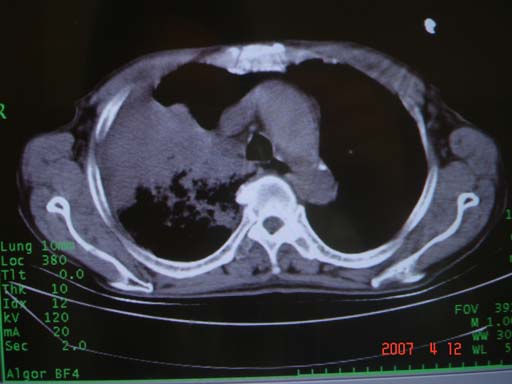

帮我 看看。男77岁咳嗽咯血2月发热2周!病人一般情况可 口痰为鲜红,有点象洗肉水(我看见他吐的痰了)

病灶局限在右肺中上叶,呈大片状实变影,内见空气支气管征,支气管分支较柔软,纵隔内未见肿大淋巴结.支持:感染性病变_1 大叶性肺炎.2 干酪性肺炎.

优先考虑右上肺干酪性肺炎并同侧中叶播散、胸腔积液。分析:右膈肌未见升高、纵隔未见明显右移,胸部各组淋巴结未见可疑肿大,中叶可见支气管铸形,肺野、肺门未见可确定肿块。

单从影像学上来看,该病人应首先考虑,右上肺感染(干酪性肺炎可能大)伴有右侧胸腔积液,理由如下:

1.病灶整体成宽基底征,而未见块状影

2.病灶内的透光区并不是含气支气管征,而像是坏死的肺组织后形成的

3.无肺不张的表现

4.纵隔那未见明显肿大淋巴结

结合病史,该病人尚需作进一步检查胸水,支气管镜,查痰等

有点象洗肉水的痰,其来源应当是实变引起的血细胞渗出导致,可见支气管气象,实变区有虫蚀状空洞,有明显胸腔积液,未见明显肺门区肿块影,考虑继发型肺结核,干酪性肺炎

右肺上叶实变,实变范围如此之大,如果用肺癌解释的化,应该是比较大的支气管开口发生完全阻塞,但观察上叶前后段支气管还是比较通畅,所以应考虑感染性病变,大叶性肺炎可能,建议抗炎治疗后复查。